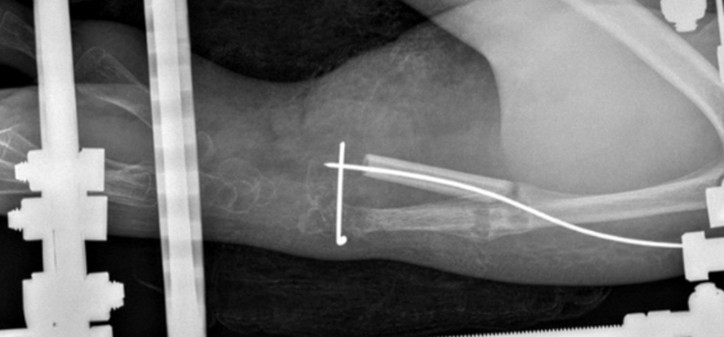

• Centralisation for radial dysplasia type 4

• Macrodactyly bilateral feet – right central ray amputation x2, left great toe amputation and on-top plasty D3 to 1